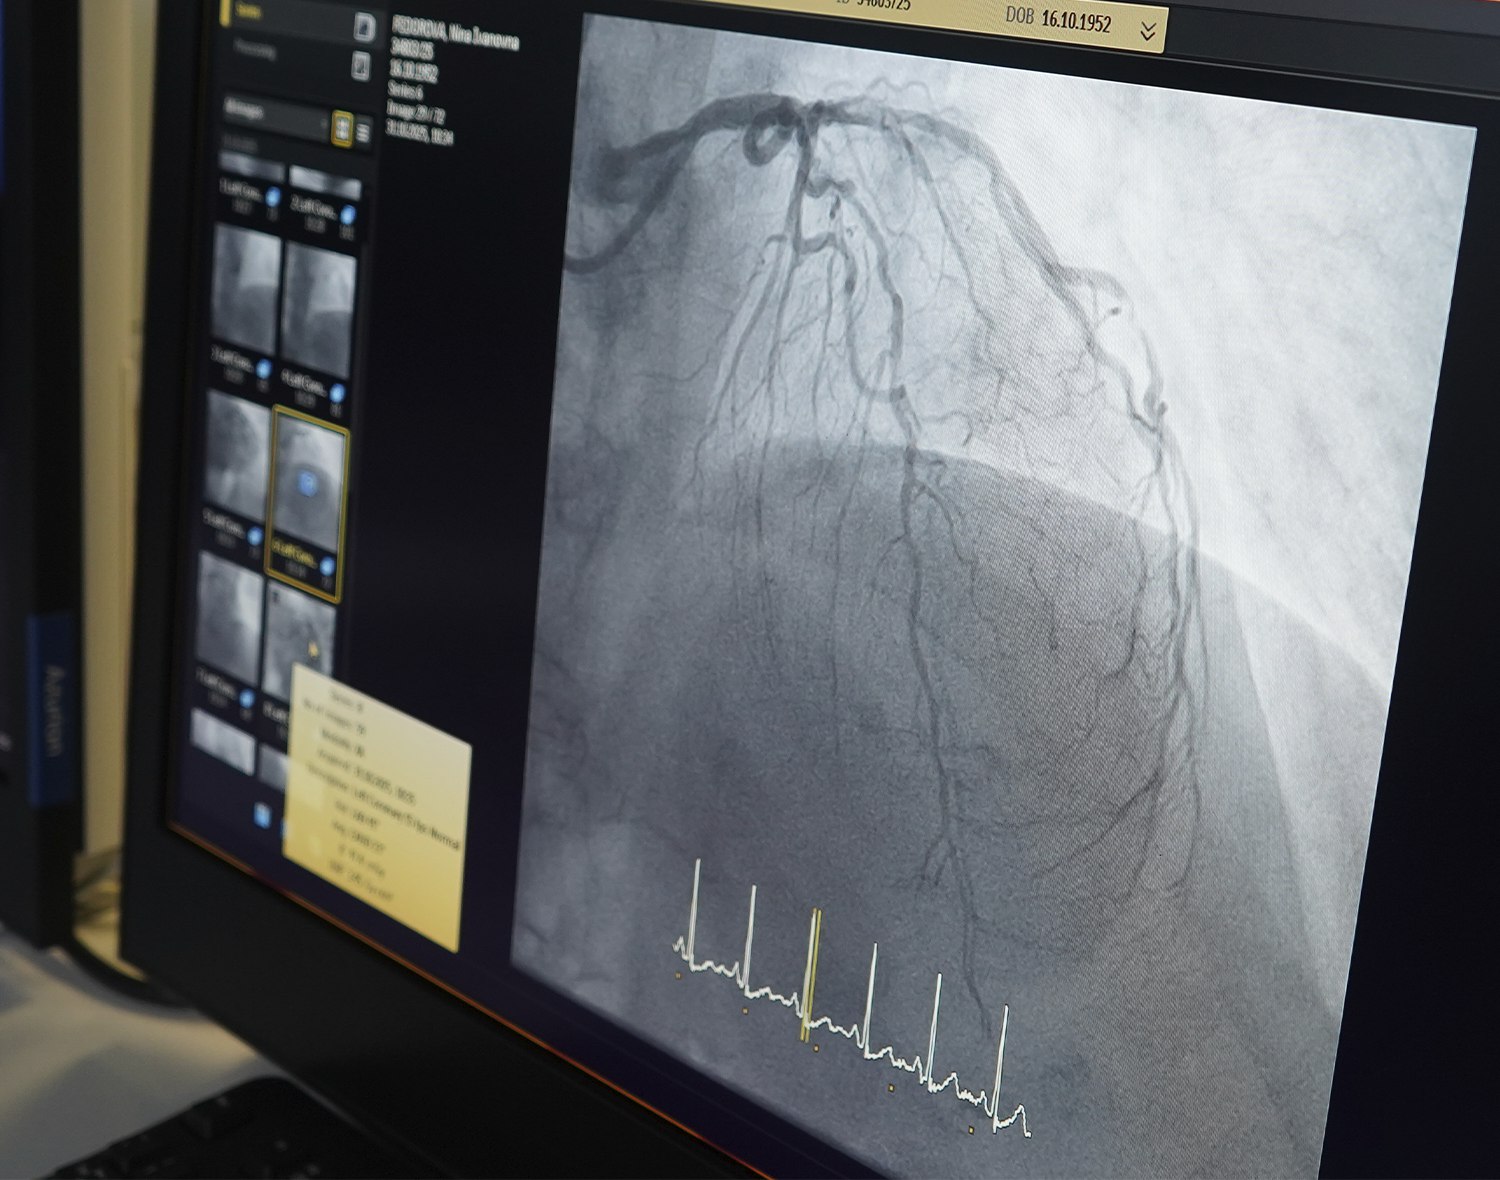

"31 октября при поддержке наставника провела операцию по стентированию коронарной артерии. Пациентку доставили на машине скорой помощи, её беспокоили боли в сердце. Было показано проведение коронарографии в срочном порядке. Операцию по имплантации стента в критическое сужение провели с местной анестезией через прокол артерии на руке", - делится молодой специалист.